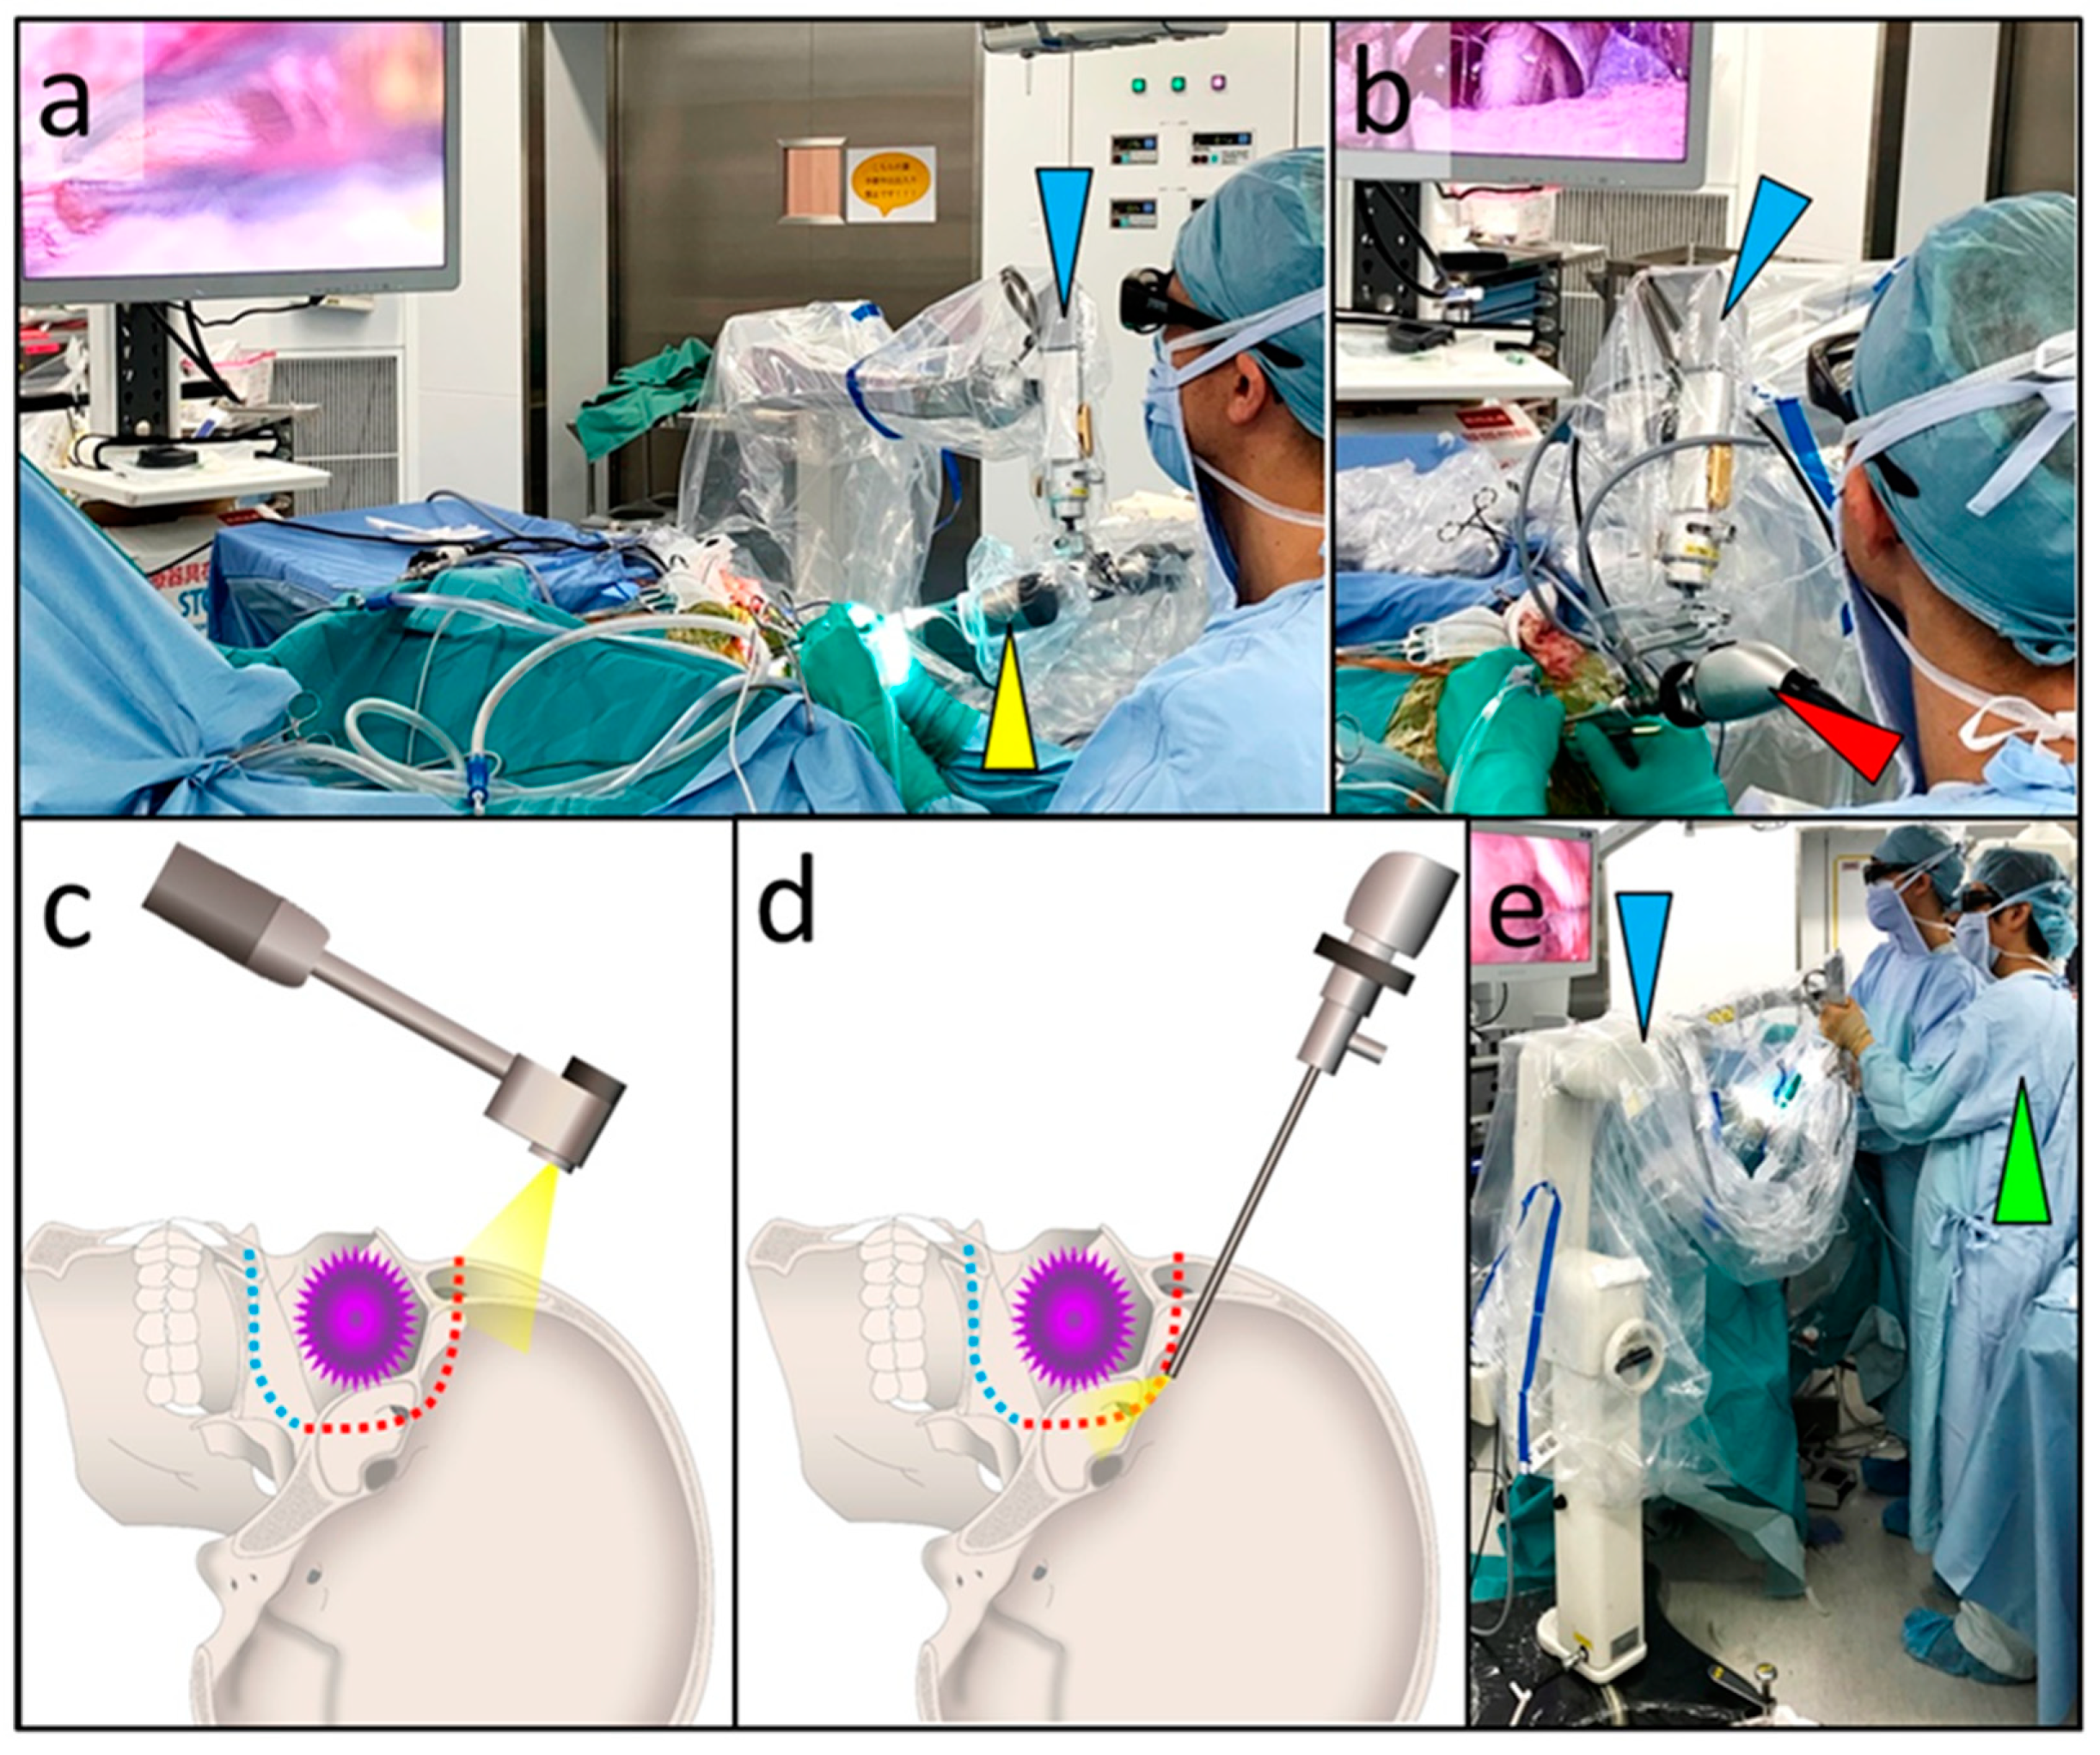

The Handbook of C-Arm Fluoroscopy-Guided Spinal Injections, Combined Exoscopic and Endoscopic Technique for Craniofacial,

Combined Exoscopic and Endoscopic Technique for Craniofacial, VSP Craniomaxillofacial Solutions | 3D Systems